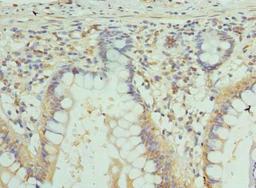

GJA4 Antibody

- Immunohistochemistry (IHC)